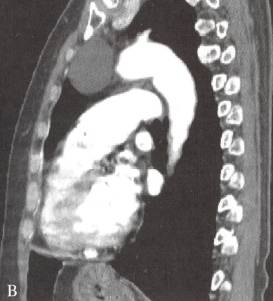

图1胸腺囊肿

女性,59岁,查体发现前纵隔肿物1周。A, B.增强CT横断面及矢状面重组图像示左前纵隔囊性肿物,边缘锐利,壁薄。术后病理为胸腺囊肿